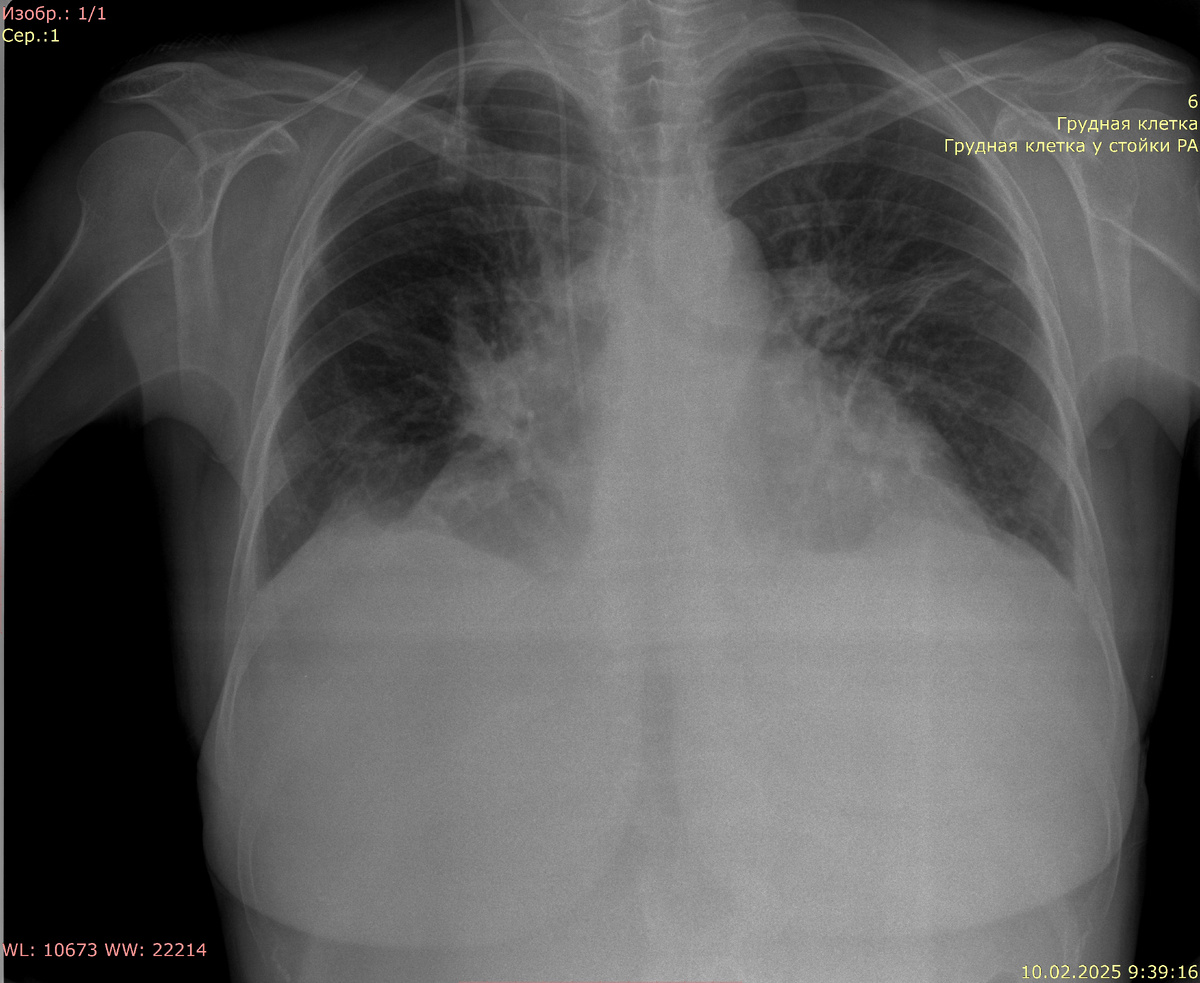

Рентгенография органов грудной клетки в прямой проекции:

Видимые дыхательные пути проходимы. Тень средостения не смещена, расширена за счет тени сердца. Корни легких четко не визуализируются. В среднем левом легочном поле линейный ателектаз. Справа в проекции корня облаковидное тяжистое образование. Синусы свободны. Костно-деструктивных изменений нет. Свободный газ не определяется. ЦВК справа, дистальный конец в проекции правого предсердия.

Заключение: плеврального выпота нет. Картина правосторонней прикорневой пневмонии (может быть прикорневым ателектазом - корреляция с клинико-лабораторными данными). ЦВК справа